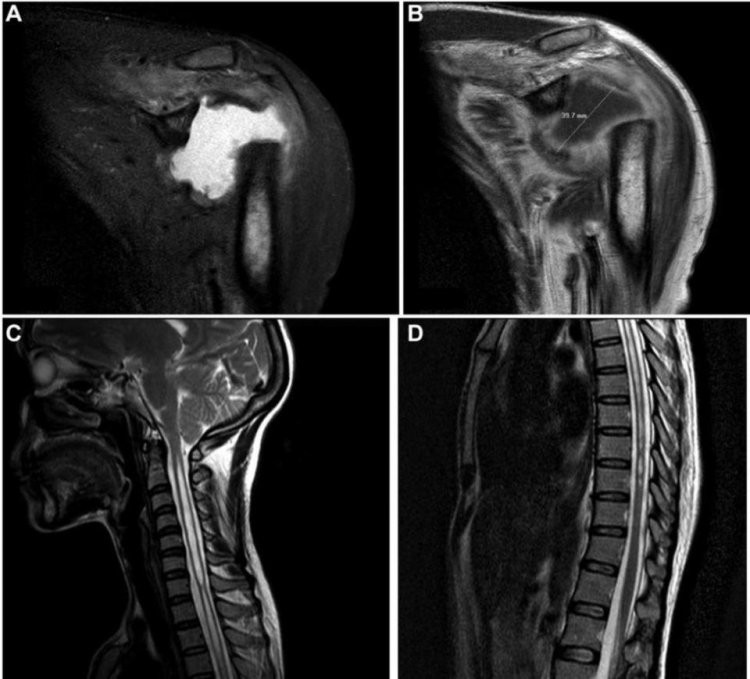

Sau khi tiến hành chụp chiếu, tia X cho thấy phần xương tròn kết nối cánh tay với vai của cô đã tiêu biến khiến nó chỉ còn một mảnh nhỏ. Các bác sĩ tại Viện Khoa học Y khoa Pondicherry ở Ấn Độ đã cho xét nghiệm nhiễm trùng, nội tiết tố cũng như trao đổi chất, tuy nhiên mọi thứ đều ở trạng thái bình thường.

Theo báo cáo trường hợp của Tạp chí Y khoa Anh, vùng xương dài ở cánh tay trên của người phụ nữ đã biến mất. Ban đầu, đội ngũ y bác sĩ nghi ngờ do bệnh về thần kinh gây ra nhưng cô hoàn toàn không hề có triệu chứng liên quan. Sự thiếu hụt các triệu chứng thần kinh khiến gây ức chế cho cơ thể, do vậy các bác sỹ chẩn đoán cô mắc chứng Gorham-Stout, một căn bệnh cực kỳ hiếm gặp khiến xương tiêu biến.

| Sau khi tiến hành chụp X quang cùng nhiều xét nghiệm khác, các bác sĩ chẩn đoán cô mắc chứng bệnh hiếm gặp có tên Gorham-Stout. |